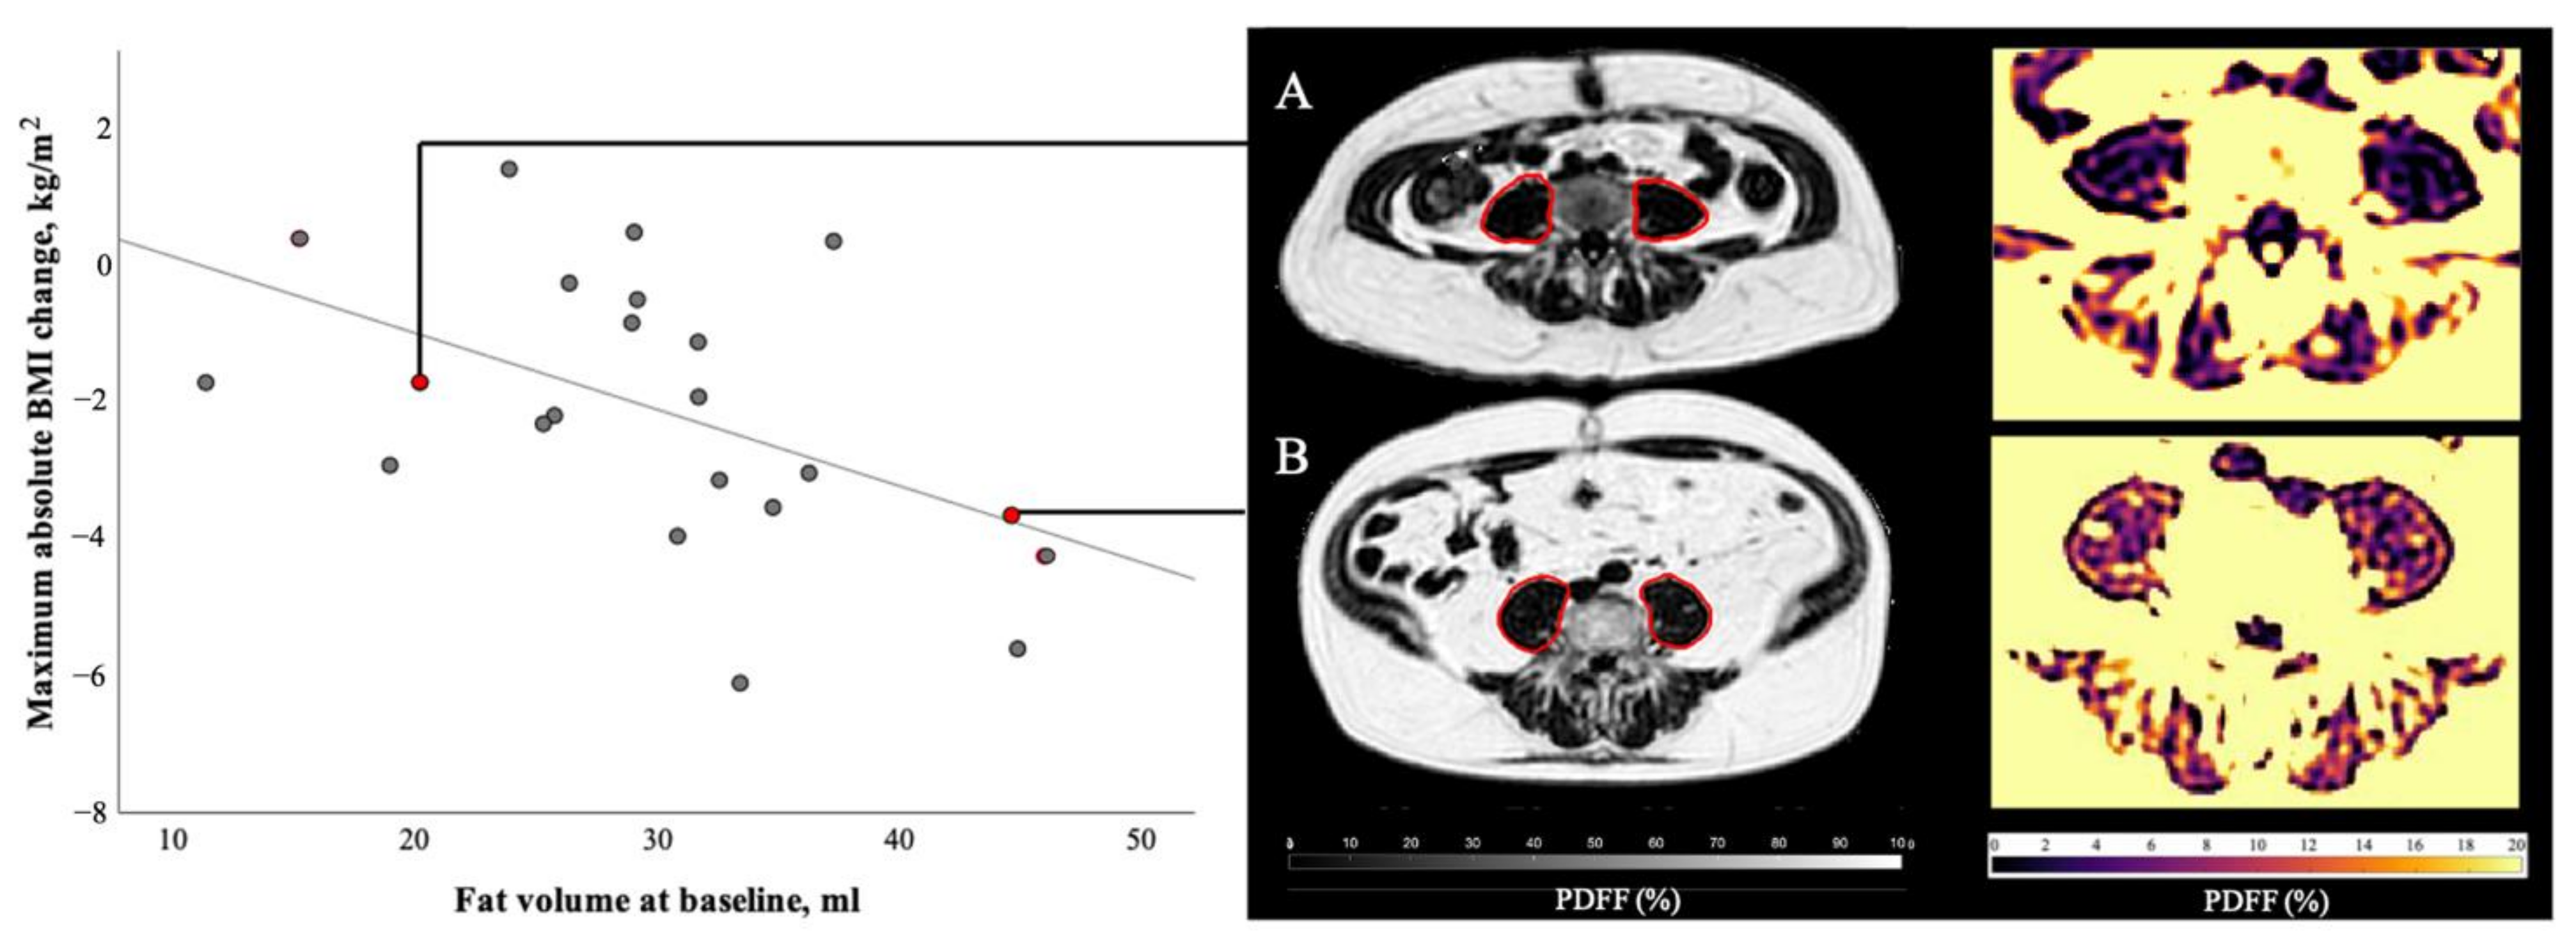

The correlation analysis of baseline muscle parameters and maximum absolute BMI change at follow-ups is described in Table 3. Importantly, when correlating the baseline measurements of skeletal muscle with the maximum changes in BMI throughout the follow-ups, an inverse correlation between the maximum BMI change and the baseline psoas fat volume could be found (r = −0.51, p = 0.02; Figure 5). Bivariate correlation with age as a control variable enhanced this correlation (r = −0.55, p < 0.01) and furthermore lead to inverse correlations between the maximum BMI change and the baseline psoas PDFF (r = −0.52, p = 0.02), as well as the erector spinae fat volume (r = −0.46, p = 0.04).

Figure 5.

Correlation of psoas muscle fat volume at baseline and maximum absolute BMI change during the course of disease. At baseline patient A (female, 48 years old, BMI 26.2 kg/m2, suffering from colorectal cancer) presented with 20.2 mL of psoas muscle fat volume, patient B (male, 64 years old, BMI 33.1 kg/m2, suffering from ductal adenocarcinoma of the pancreas) with 44.6 mL of psoas muscle fat volume. During the course of this study, patient A lost 1.7 BMI points and patient B lost 3.7 BMI points. Statistical analysis of all 22 patients with follow-ups revealed a significant correlation (r = −0.51, p = 0.02) between baseline psoas fat volume and maximum BMI change during follow-ups.

Correlating the baseline measurements of skeletal muscle per muscle section with the maximum changes in BMI revealed an inverse correlation between BMI change and psoas baseline muscle parameters of the distal muscle section. The muscle volume, contractile tissue volume and fat volume of the distal muscle section showed significant correlation with maximum BMI change (r = −0.44, p = 0.04, r = −0.44, p = 0.04, r = −0.56, p < 0.01). Psoas fat volume of the proximal muscle section also correlated with maximum BMI change (r = −0.44, p = 0.04), and partial correlation with age as a control variable improved this correlation (r = −0.53, p = 0.01). When correlation analysis of erector spinae muscle baseline parameters was conducted, a correlation between maximum BMI change and muscle volume of middle and distal muscle section (r = −0.43, p = 0.05, r = −0.44, p = 0.04), contractile tissue volume of the distal section (r = −0.46, p = 0.03) and fat volume of the proximal section (r = −0.49, p = 0.02) was found. Adding sex as a covariate instead of age did not lead to any significant correlations between the maximum BMI change and the skeletal muscle measurements.